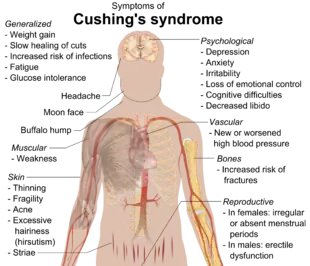

Cushing's syndrome is a collection of signs and symptoms due to prolonged exposure to glucocorticoids such as cortisol.[4][9][10] Signs and symptoms may include high blood pressure, abdominal obesity but with thin arms and legs, reddish stretch marks, a round red face due to facial plethora,[11] a fat lump between the shoulders, weak muscles, weak bones, acne, and fragile skin that heals poorly.[12][2] Women may have more hair and irregular menstruation.[2] Occasionally there may be changes in mood, headaches, and a chronic feeling of tiredness.[2]

Symptoms include rapid weight gain, particularly of the trunk and face with sparing of the limbs (central obesity). Common signs include the growth of fat pads along the collarbone, on the back of the neck ("buffalo hump" or lipodystrophy), and on the face ("moon face"). Other symptoms include excess sweating, dilation of capillaries, thinning of the skin (which causes easy bruising and dryness, particularly the hands) and mucous membranes, purple or red striae (the weight gain in Cushing's syndrome stretches the skin, which is thin and weakened, causing it to hemorrhage) on the trunk, buttocks, arms, legs, or breasts, proximal muscle weakness (hips, shoulders), and hirsutism (facial male-pattern hair growth), baldness and/or extremely dry and brittle hair. In rare cases, Cushing's can cause hypocalcemia. The excess cortisol may also affect other endocrine systems and cause, for example, insomnia, inhibited aromatase, reduced libido, impotence in men, and amenorrhoea, oligomenorrhea and infertility in women due to elevations in androgens. Studies have also shown that the resultant amenorrhea is due to hypercortisolism, which feeds back onto the hypothalamus resulting in decreased levels of GnRH release.[23]

Many of the features of Cushing's are those seen in metabolic syndrome, including insulin resistance, hypertension, obesity, and elevated blood levels of triglycerides.[24]

Cognitive conditions, including memory and attention dysfunctions, as well as depression, are commonly associated with elevated cortisol,[25] and may be early indicators of exogenous or endogenous Cushing's. Depression and anxiety disorders are also common.[26]

Other striking and distressing skin changes that may appear in Cushing's syndrome include facial acne, susceptibility to superficial fungus (dermatophyte and malassezia) infections, and the characteristic purplish, atrophic striae on the abdomen.[27]: 500

Other signs include increased urination (and accompanying increased thirst), persistent high blood pressure (due to cortisol's enhancement of epinephrine's vasoconstrictive effect) and insulin resistance (especially common with ACTH production outside the pituitary), leading to high blood sugar and insulin resistance which can lead to diabetes mellitus. Insulin resistance is accompanied by skin changes such as acanthosis nigricans in the axilla and around the neck, as well as skin tags in the axilla. Untreated Cushing's syndrome can lead to heart disease and increased mortality. Cortisol can also exhibit mineralocorticoid activity in high concentrations, worsening the hypertension and leading to hypokalemia (common in ectopic ACTH secretion) and hypernatremia (increased Na+ ions concentration in plasma). Furthermore, excessive cortisol may lead to gastrointestinal disturbances, opportunistic infections, and impaired wound healing related to cortisol's suppression of the immune and inflammatory responses. Osteoporosis is also an issue in Cushing's syndrome since osteoblast activity is inhibited. Additionally, Cushing's syndrome may cause sore and aching joints, particularly in the hip, shoulders, and lower back.

- Rapid weight gain

- Moodiness, irritability, or depression

- Muscle and bone weakness

- Memory and attention dysfunction

- Osteoporosis

- Diabetes mellitus

- Hypertension

- Immune suppression

- Sleep disturbances

- Menstrual disorders such as amenorrhea in women

- Infertility in women

- Impotence in men

- Hirsutism

- Baldness

- Hypercholesterolemia